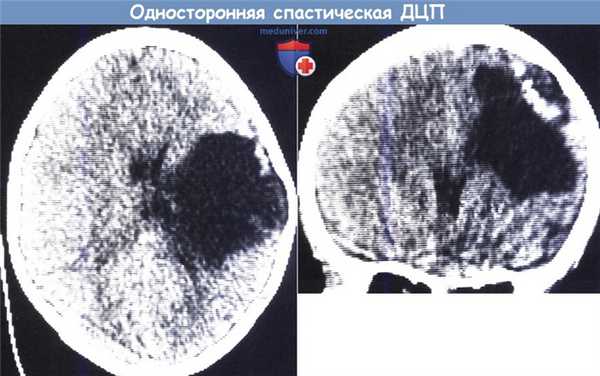

Кистозное размягчение в бассейне левой средней мозговой артерии у 6-летней девочки с правосторонней врожденной гемиплегией:

КТ (сверху — аксиальная проекция, снизу — фронтальная проекция).

Заметно расширение свода черепа, истончение кости на уровне полости и области кальцификации сверху и снаружи от повреждения.